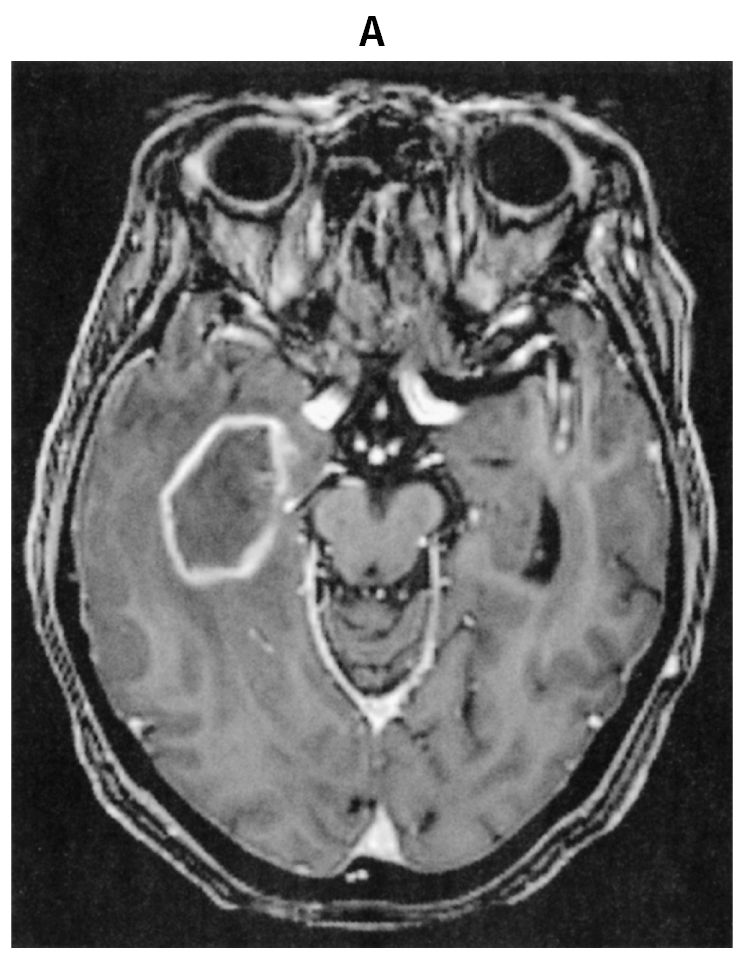

69歳の女性。悪心を主訴に来院した。悪心は3日前から時々自覚していた。既往歴に高血圧症と糖尿病があり,いずれも内服治療中である。慢性腎不全のため5年前に生体腎移植を受け,免疫抑制薬を投与されている。喫煙歴はない。意識レベルはJCSⅠ-1。身長150cm,体重41kg。神経診察で異常を認めない。血液所見:赤血球400万,Hb 12.3g/dL,Ht 41%,白血球6,500,血小板18万。血液生化学所見:総蛋白6.9g/dL,アルブミン4.4g/dL,総ビリルビン0.8mg/dL,AST 22U/L,ALT 10U/L,LD 237U/L(基準124~222),尿素窒素19mg/dL,クレアチニン0.9mg/dL,血糖118mg/dL,HbA1c 6.2%(基準4.9~6.0),Na 140mEq/L,K 4.7mEq/L,Cl 107mEq/L,CEA 2.9ng/mL(基準5以下),CA19-9 2U/mL未満(基準37以下),ProGRP 80pg/mL(基準81以下)。免疫血清学所見:可溶性IL-2受容体685U/mL(基準157~474),CRP 0.1mg/dL。頭部造影MRIのT1強調像(A)と頭部単純MRIのFLAIR像(B)とを下に示す。胸腹部造影CTで異常を認めない。画像所見をもとに病変の生検術を施行した。生検H-E染色標本(C)を下に示す。生検組織内にて増殖を認める細胞は,抗CD20抗体を用いた免疫染色にてB細胞の表面抗原が陽性であった。